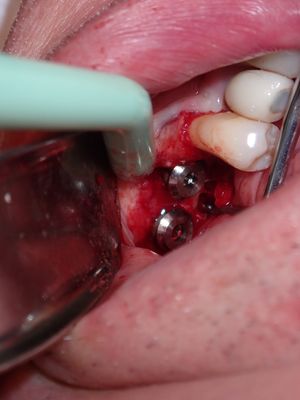

large amount of bone loss at time of exo 36/37 done 2 months ago. Good healing of bone except for small socket area at 36 region. buccal bone lower than palatal about 1mm, decided to place tissue level implants opposed to grafting, gaining back height is unlikely, difficult access case with large tongue. Implants placed with 36 about 1.5mm buccal exposed, 37, .5mm mesial exposed, healing abutments palced grafted all sites with sticky bone followed by collagen membrane soaked in prf fluid, 2 holes cut for implants. additonal fibrin membrance placed on buccal prior to suturing.